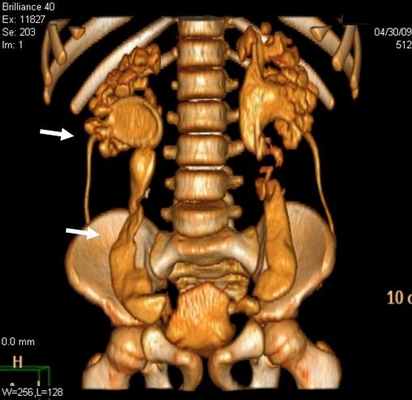

Уретероцеле обнаружено у 3 (8,1%) пациентов из 37. Этот порок уретеровезикального сегмента на МСКТ характеризовался с кистовидным расширением внутрипузырного сегмента мочеточника. При этом отчетливо определяется округлая полость, вдающаяся в просвет мочевого пузыря (рис. 3).

Хотя по литературным данным эктопия устьев мочеточника наблюдается чаще, чем другие варианты пороков данной области, но нами были диагностированы у 5 (13,5%) пациентов. Эктопия устьев мочеточника на МСКТ характеризовался удвоением мочеточника у 3 пациентов и эктопическим расположением устьев мочеточника у всех больных.

Рис 3. МСКТ картина уретероцеле. Трехмерная реконструкция. Удвоение почек и мочеточника справа (a) и уретероцеле слева (б)

Во всех наблюдениях устья мочеточников открывались в мочевой пузырь. В отличие от экскреторной урографии на МСКТ четко определяются изменения со стороны почек и мочеточника, особенно при трехмерной реконструкции.

У 2 пациентов с эктопией устья мочеточника также диагностирована гипоплазия устья мочеточника со стенозированием (рис 3.).